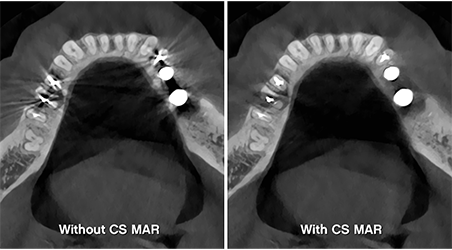

Artifact-free images

Game-changing CS MAR3 technology allows you to instantly compare images with and without metal artifact reduction to ensure the most accurate diagnosis and reduce the risk of misinterpretation.

3 - Option